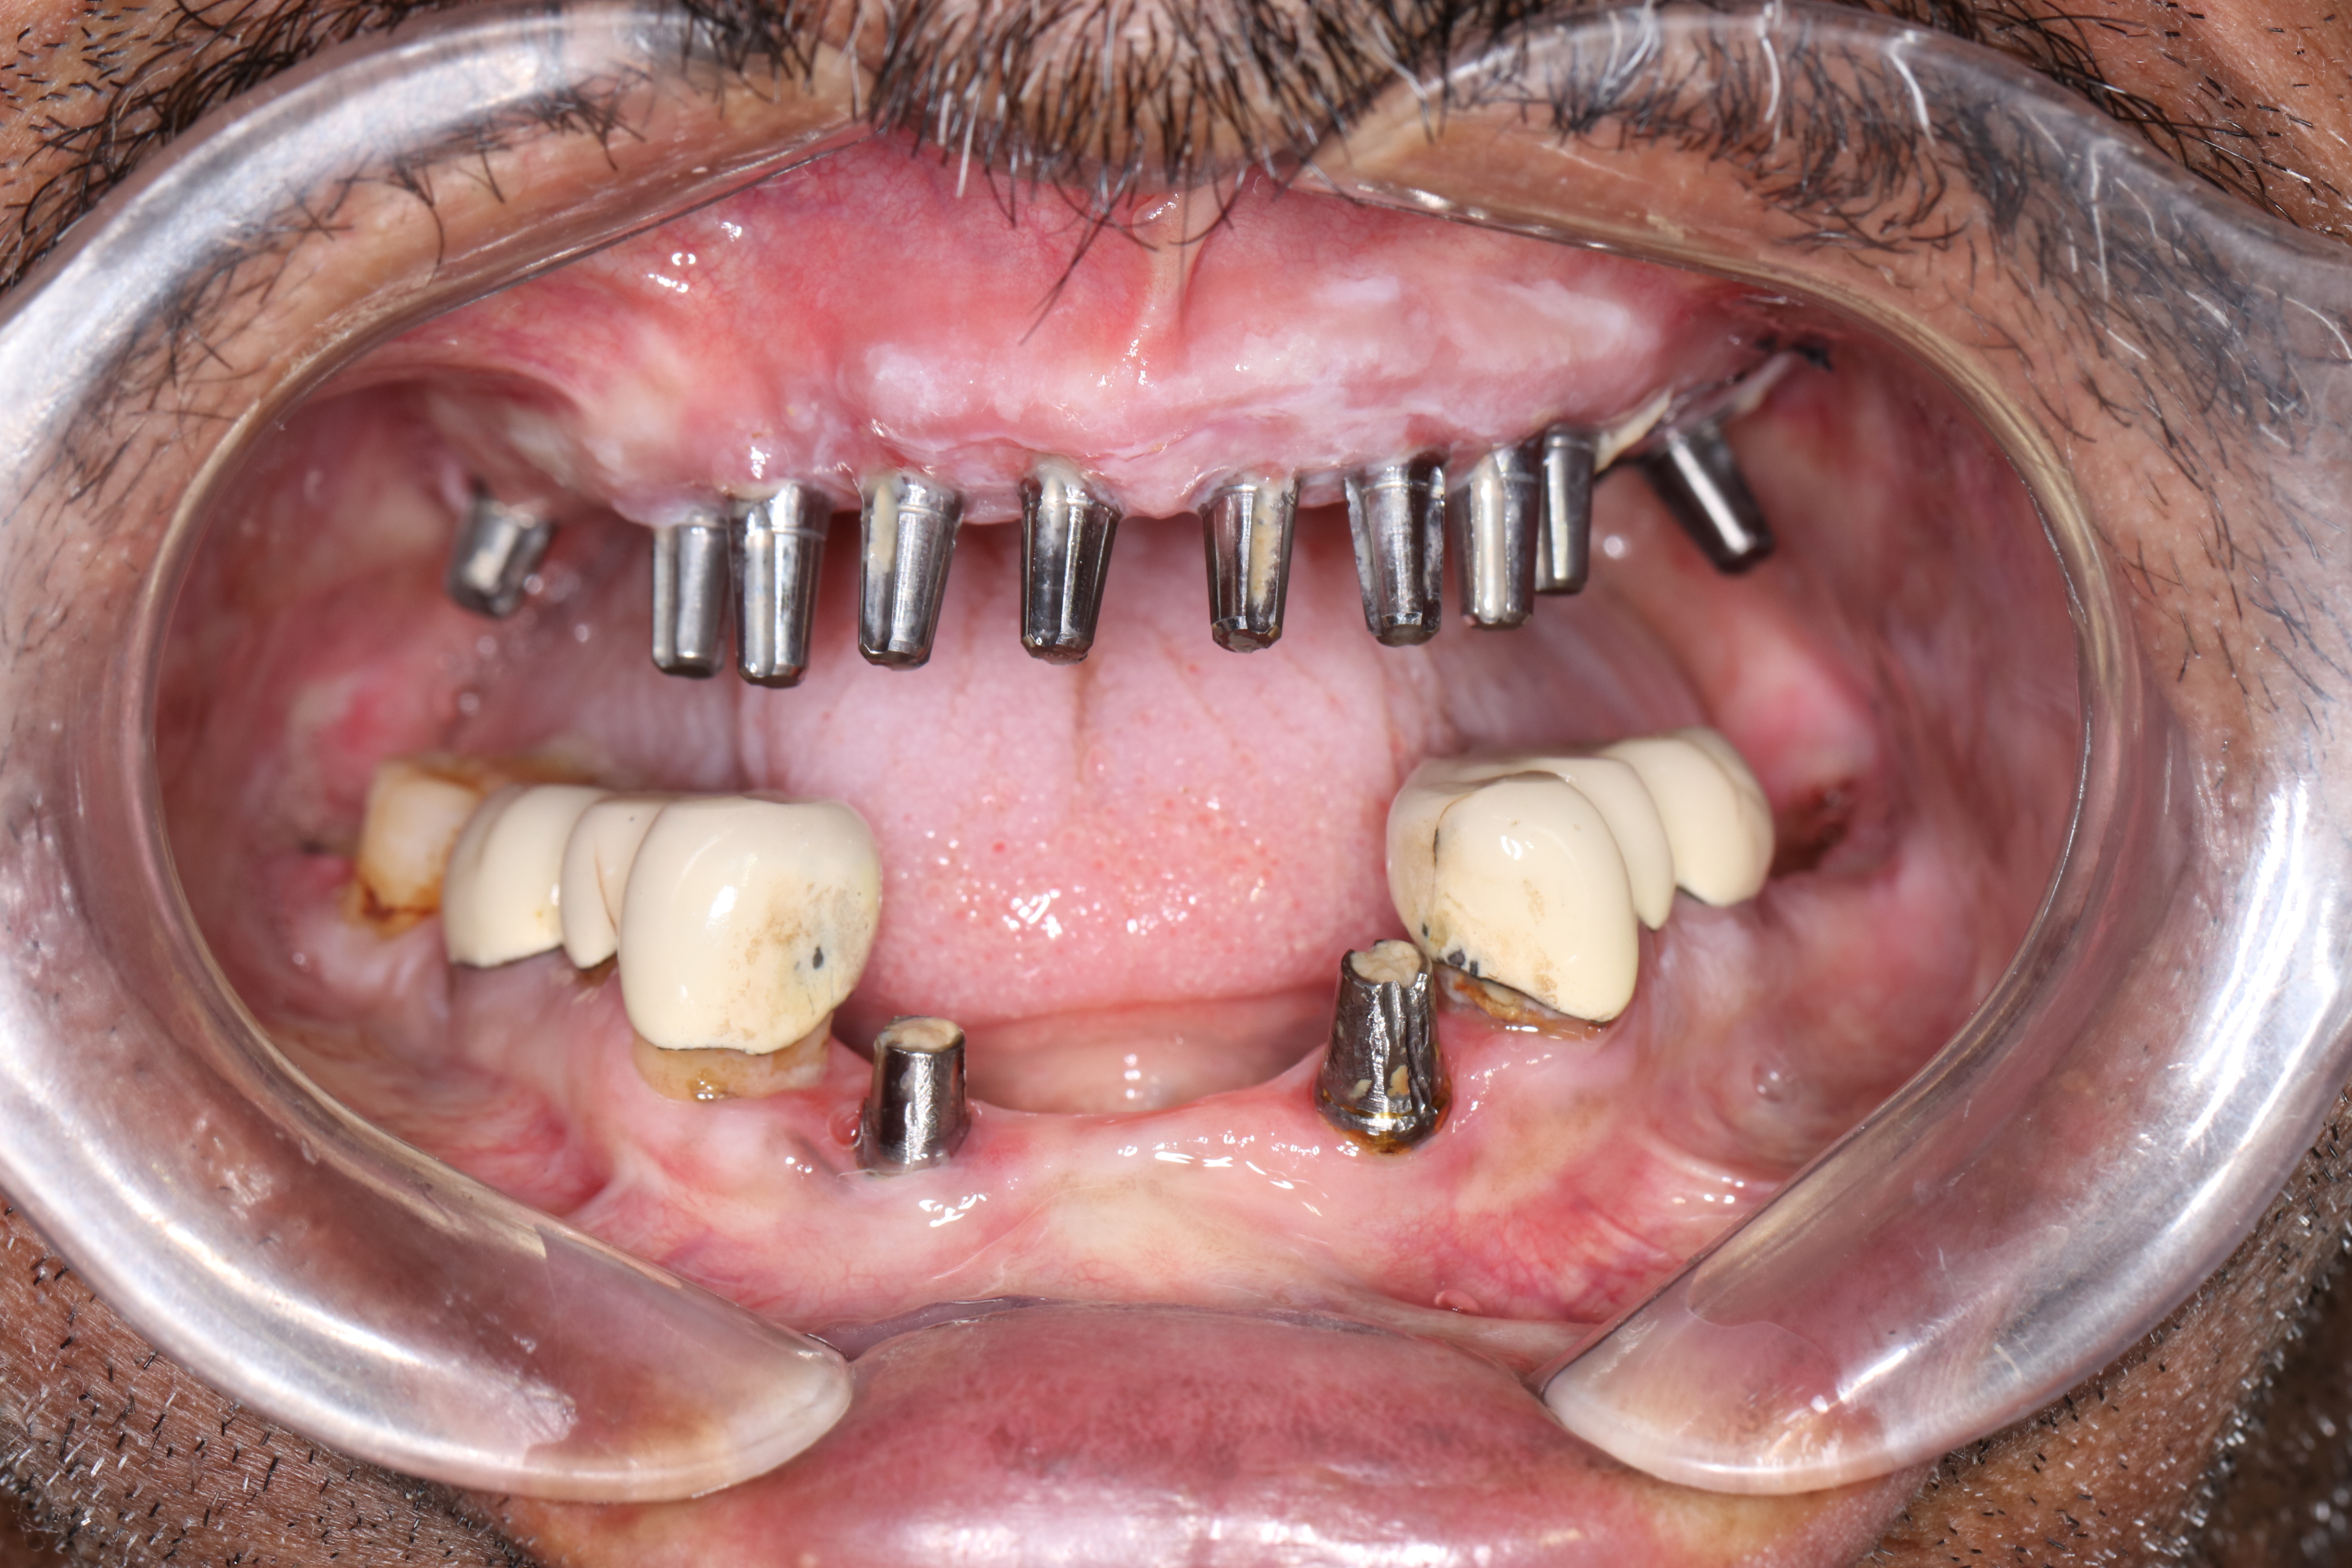

At Jani's Implant Centre And Smile Studio in Bhavnagar and Ahemdabad, Gujarat, a combination of basal implants with crestal implants are widely used to give the desired function.

The pterygoid implant is used to avoid the usage of cantilevers. Owing to this we can easily give 14 teeth which include the second molars. Depending on the health of the individual, the status of oral health and the amount of bone available 8-10 implants are placed to give a full set of dental implants in the upper jaw (full arch). This means that with the replacement of even second molars the quality of chewing improves and becomes more efficient like natural teeth.

With our time tested and trusted method of Permanent teeth in 3 days using dental basal implants. Cortical implants, pterygoid implants and zygomatic implants the need for bone augmentation and bone grafting is obliterated.